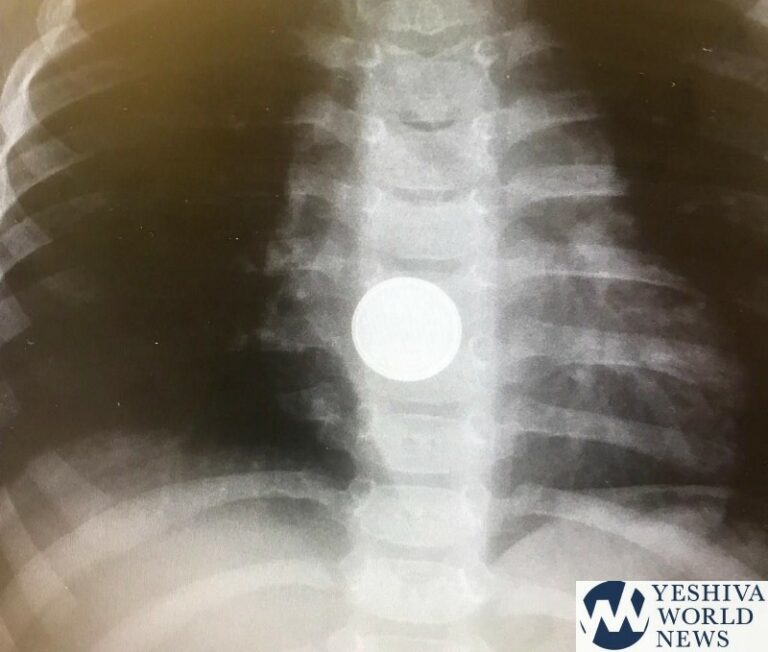

New guidelines from Shaare Zedek Hospital in Jerusalem state that if a child ingests a battery and s/he is over a year old, the child should be given honey. Recent